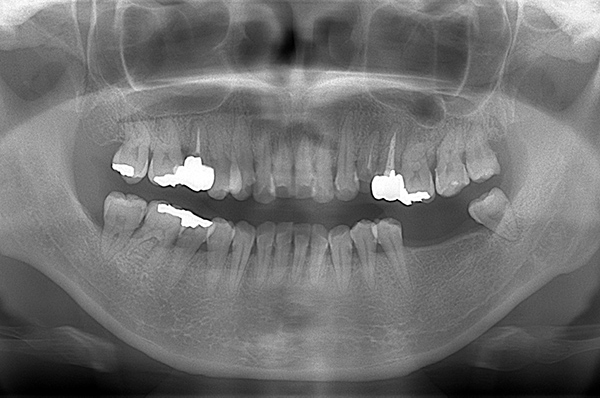

レントゲン写真(治療前)

【担当医師所見】

根の治療を3本すでに治療されています。1本根の奥の詰め物が疎になっていますので、根の部分の再治療も行う必要がありそうです。銀歯の中で虫歯になっているものもあります。